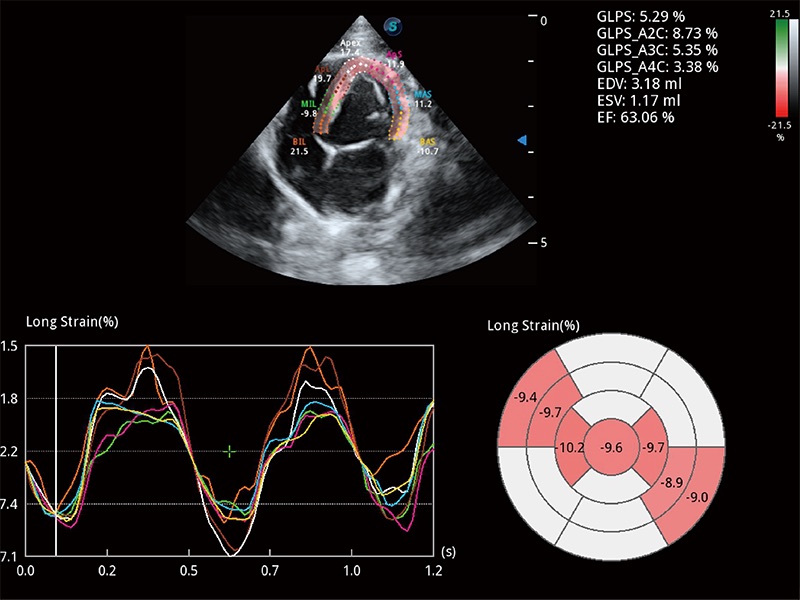

通过心肌识别技术与二维斑点追踪技术相结合,对心脏的超声图像进行量化分析。计算心肌17个节段的应变、应变率、速度、位移等,并通过牛眼图的形式进行呈现。